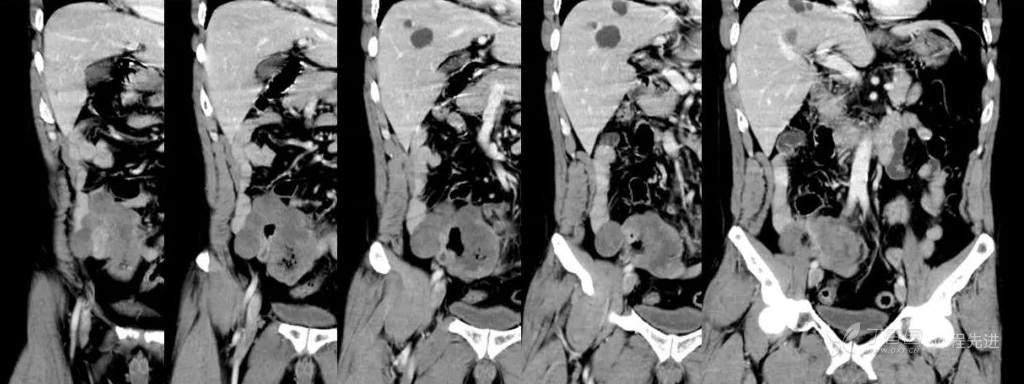

冠状位